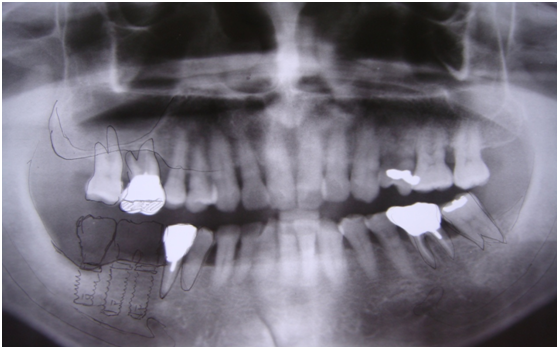

完成後大約半年至一年進行一次例行性追蹤檢查,並無特別問題。以下為96/08/13時的追蹤小片,可以見到當時三顆植體的骨高度並無顯著變化。但右下第一小臼齒此時發現有搖動度增加的情形,當時對該顆牙做了咬合調整,降低咬合功能負荷,希望能有所改善。

96/08/13

患者之後於96/11/08在右下第一小臼齒與植體間有膿胞產生,並於97/02/21確認右下第一小臼齒有根裂的情形,因此在97/02/29拔除此牙;經過將近半年後,於97/09/23放置一顆植體於此位置

97/02/21 確定根裂時拍的片子

97/02/21